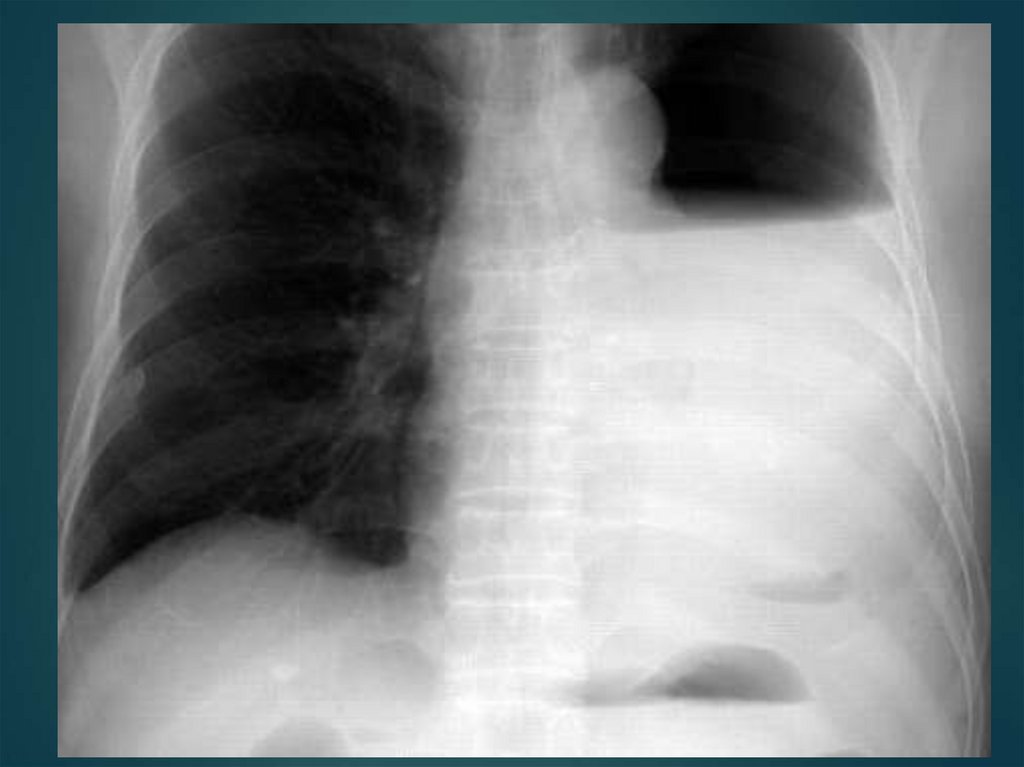

Гемоторакс–

Клиника:

62. Гемоторакс–

скопление крови в плевральной полости в

результате внутреннего кровотечения при

ранении ткани легкого, повреждении

межреберных артерий (переломы ребер).

64. Клиника:

зависит от количества излившейся крови и темпа

внутриплеврального кровотечения.

Небольшое количество крови вызывает боль в

груди, кашель.

По мере скопления крови возникает одышка,

цианоз, вынужденное сидячее положение

пациента.

Значительная кровопотеря сопровождается

тахикардией, появляется бледность кожных

покровов, слабость, боль в грудной клетке,

падение артериального давления, учащение

пульса, кашель.

При аускультации ослабление дыхания, при

перкуссии притупление перкуторного звука внизу

на стороне поражения.

При поступлении больного в стационар:

Новокаиновая блокада;

Пункция плевральной полости;

Дренирование плевральной полости по Бюлау